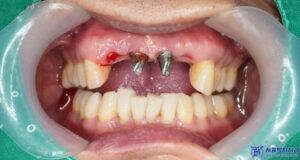

환자분의 기존 보철물과 지대주를 제거하고

보철물 제작을 위한 스캔을 진행하였습니다.

보철물 재제작 후 사진입니다.

제거 후 보철물 제작까지

단 2일 만에 치료를 마무리 하였으며,

환자분께서도 심미적으로

매우 만족해 하셨습니다.